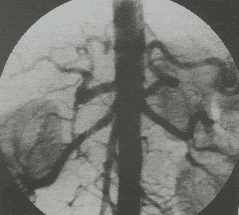

Chụp số hóa xóa nền (Digital Subtraction Angiography - DSA) là một kỹ thuật chụp hình mạch máu mới bằng tia X. Đây là phương pháp Chẩn đoán hình ảnh được kết hợp từ chụp X-quang và xử lý số sử dụng thuật toán để xóa nền trên 2 ảnh thu nhận được trước và sau khi tiêm chất cản quang vào cơ thể người bệnh. Mục đích của kỹ thuật này là nghiên cứu mạch máu trong cơ thể và thấy rõ hơn các thương tổn và bệnh lý mạch máu trước khi chỉ định can thiệp mạch.

- Chụp mạch: đưa ống thông vào tĩnh mạch trên gan, chụp tĩnh mạch cửa bằng cách bơm trào ngược thuốc đối quang từ tĩnh mạch trên gan qua nhu mô gan vào tĩnh mạch.